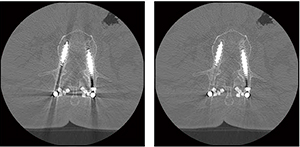

当社が2015年に製品化した「Supria Grande」は,64列CTでありながら,3点ユニット構成でコンパクトな設計で開口径も広く,サブミリで全身を高速撮影できる能力を持っている(図1)。AEC機能“IntelliEC”や体内金属が原因で発生するアーチファクトを補正する機能“HiMAR”(図2)も標準で搭載し,Aiで求められるCT撮影には必要十分な機能を備えていると考える。

図2 金属アーチファクト補正の例 |